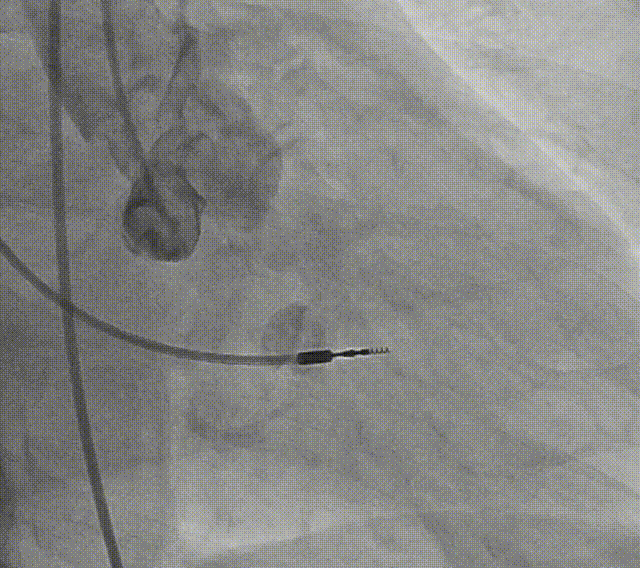

患者病史 术前超声提示:主动脉瓣退行性病变;中-重度狭窄并轻度返流;中-重度三尖瓣返流;中度肺高压 术前CT 三叶瓣,瓣叶增厚轻度钙化,右无交界有粘连,预计可以扩开,主动脉根部直径23.7mm,LVOT直径24.3mm,呈直筒型;双侧冠脉开口高度可,瓣叶长度小于冠脉开口上缘到主动脉根部的距离;窦部空间可,STJ、升主动脉内径可;主动脉水平夹角43.6°,非横位心;主动脉弓角、弓距可,左室内径可;外周入路无明显迂曲,有零星散状钙化,双侧股动脉内径可,均能通过20F大鞘,右股低分叉。 手术策略 推荐右侧股动脉为主入路使用20F大鞘,左侧股动脉为辅入路,右股分叉上方1cm穿刺;推荐使用22mm球囊预扩,预装AV26瓣膜,备AV29瓣膜,初始定位为真实瓣环上方3mm,瓣膜释放过程中释放张力使其自然下滑,工作位观察瓣膜稳定性,最终理想位置为零位;左右重合位:RAO23°CAU32°;右窦居中位:LAO5°CAU12°;左冠切线位:LAO34°CRA14°。 手术过程 术中右股动脉痉挛,内径变为3.8mm,遂更换左腋动脉入路;18球囊预扩,后植入AV26 ProStyle A®瓣膜;瓣膜精准释放于目标位置,超声显示无明显瓣周漏,血流动力学即刻改善。 术中右股动脉痉挛,内径变为3.8mm,更换左腋动脉 主动脉根部造影 18球囊预扩 初始定位 工作位观察 术后即刻表现:无瓣周漏,术后峰值压差10mmHg 术后3天复查超声峰值压差14mmHg Prostyle A®预装干瓣——助力临床最优化解决方案: 轻松过弓,精准可控:该病例经左腋动脉入路,输送系统较细的尺寸+柔顺的输送系统通过性能得到了很好的验证; 释放稳定:平衡的径向支撑力降低了释放过程中的张力,流入端小锥角设计能够迅速锚定贴边,80%可回收使得观察位和释放后的位置差距减少,大大提高了释放过程中的精准性,能够轻松应对高难度病例; 预装干瓣 便捷顺安:金仕生物专利抗钙化技术运用纳米技术去除组织内的细胞碎片和磷脂,封闭游离醛基,从根本上阻断了瓣膜钙化的多项因素,显著提升了瓣膜的耐久性;同时,相比较传统戊二醛保存方式,干式存储最大限度的保留心包的亲水亲油平衡,还原组织天然曲柔性,进一步保障了瓣叶开合,保证长期耐久性; 谢年谨教授 广东省人民医院 谢年谨教授指出:“对于外周血管条件较差的心脏瓣膜病患者,腋动脉路径凭借其更直接的解剖通路与更稳定的输送环境,为手术安全提供了重要保障,尤其适用于股动脉入路失败的复杂病例。该路径不仅能显著降低血管损伤、出血等并发症风险,还能通过更清晰的操作视野提升手术成功率;尤其在高龄、动脉硬化严重的患者群体中,腋动脉路径的适应性优势更为突出。 专家简介 荆志成 广东省人民医院 谢年谨 广东省人民医院 刘勇 广东省人民医院 · END ·